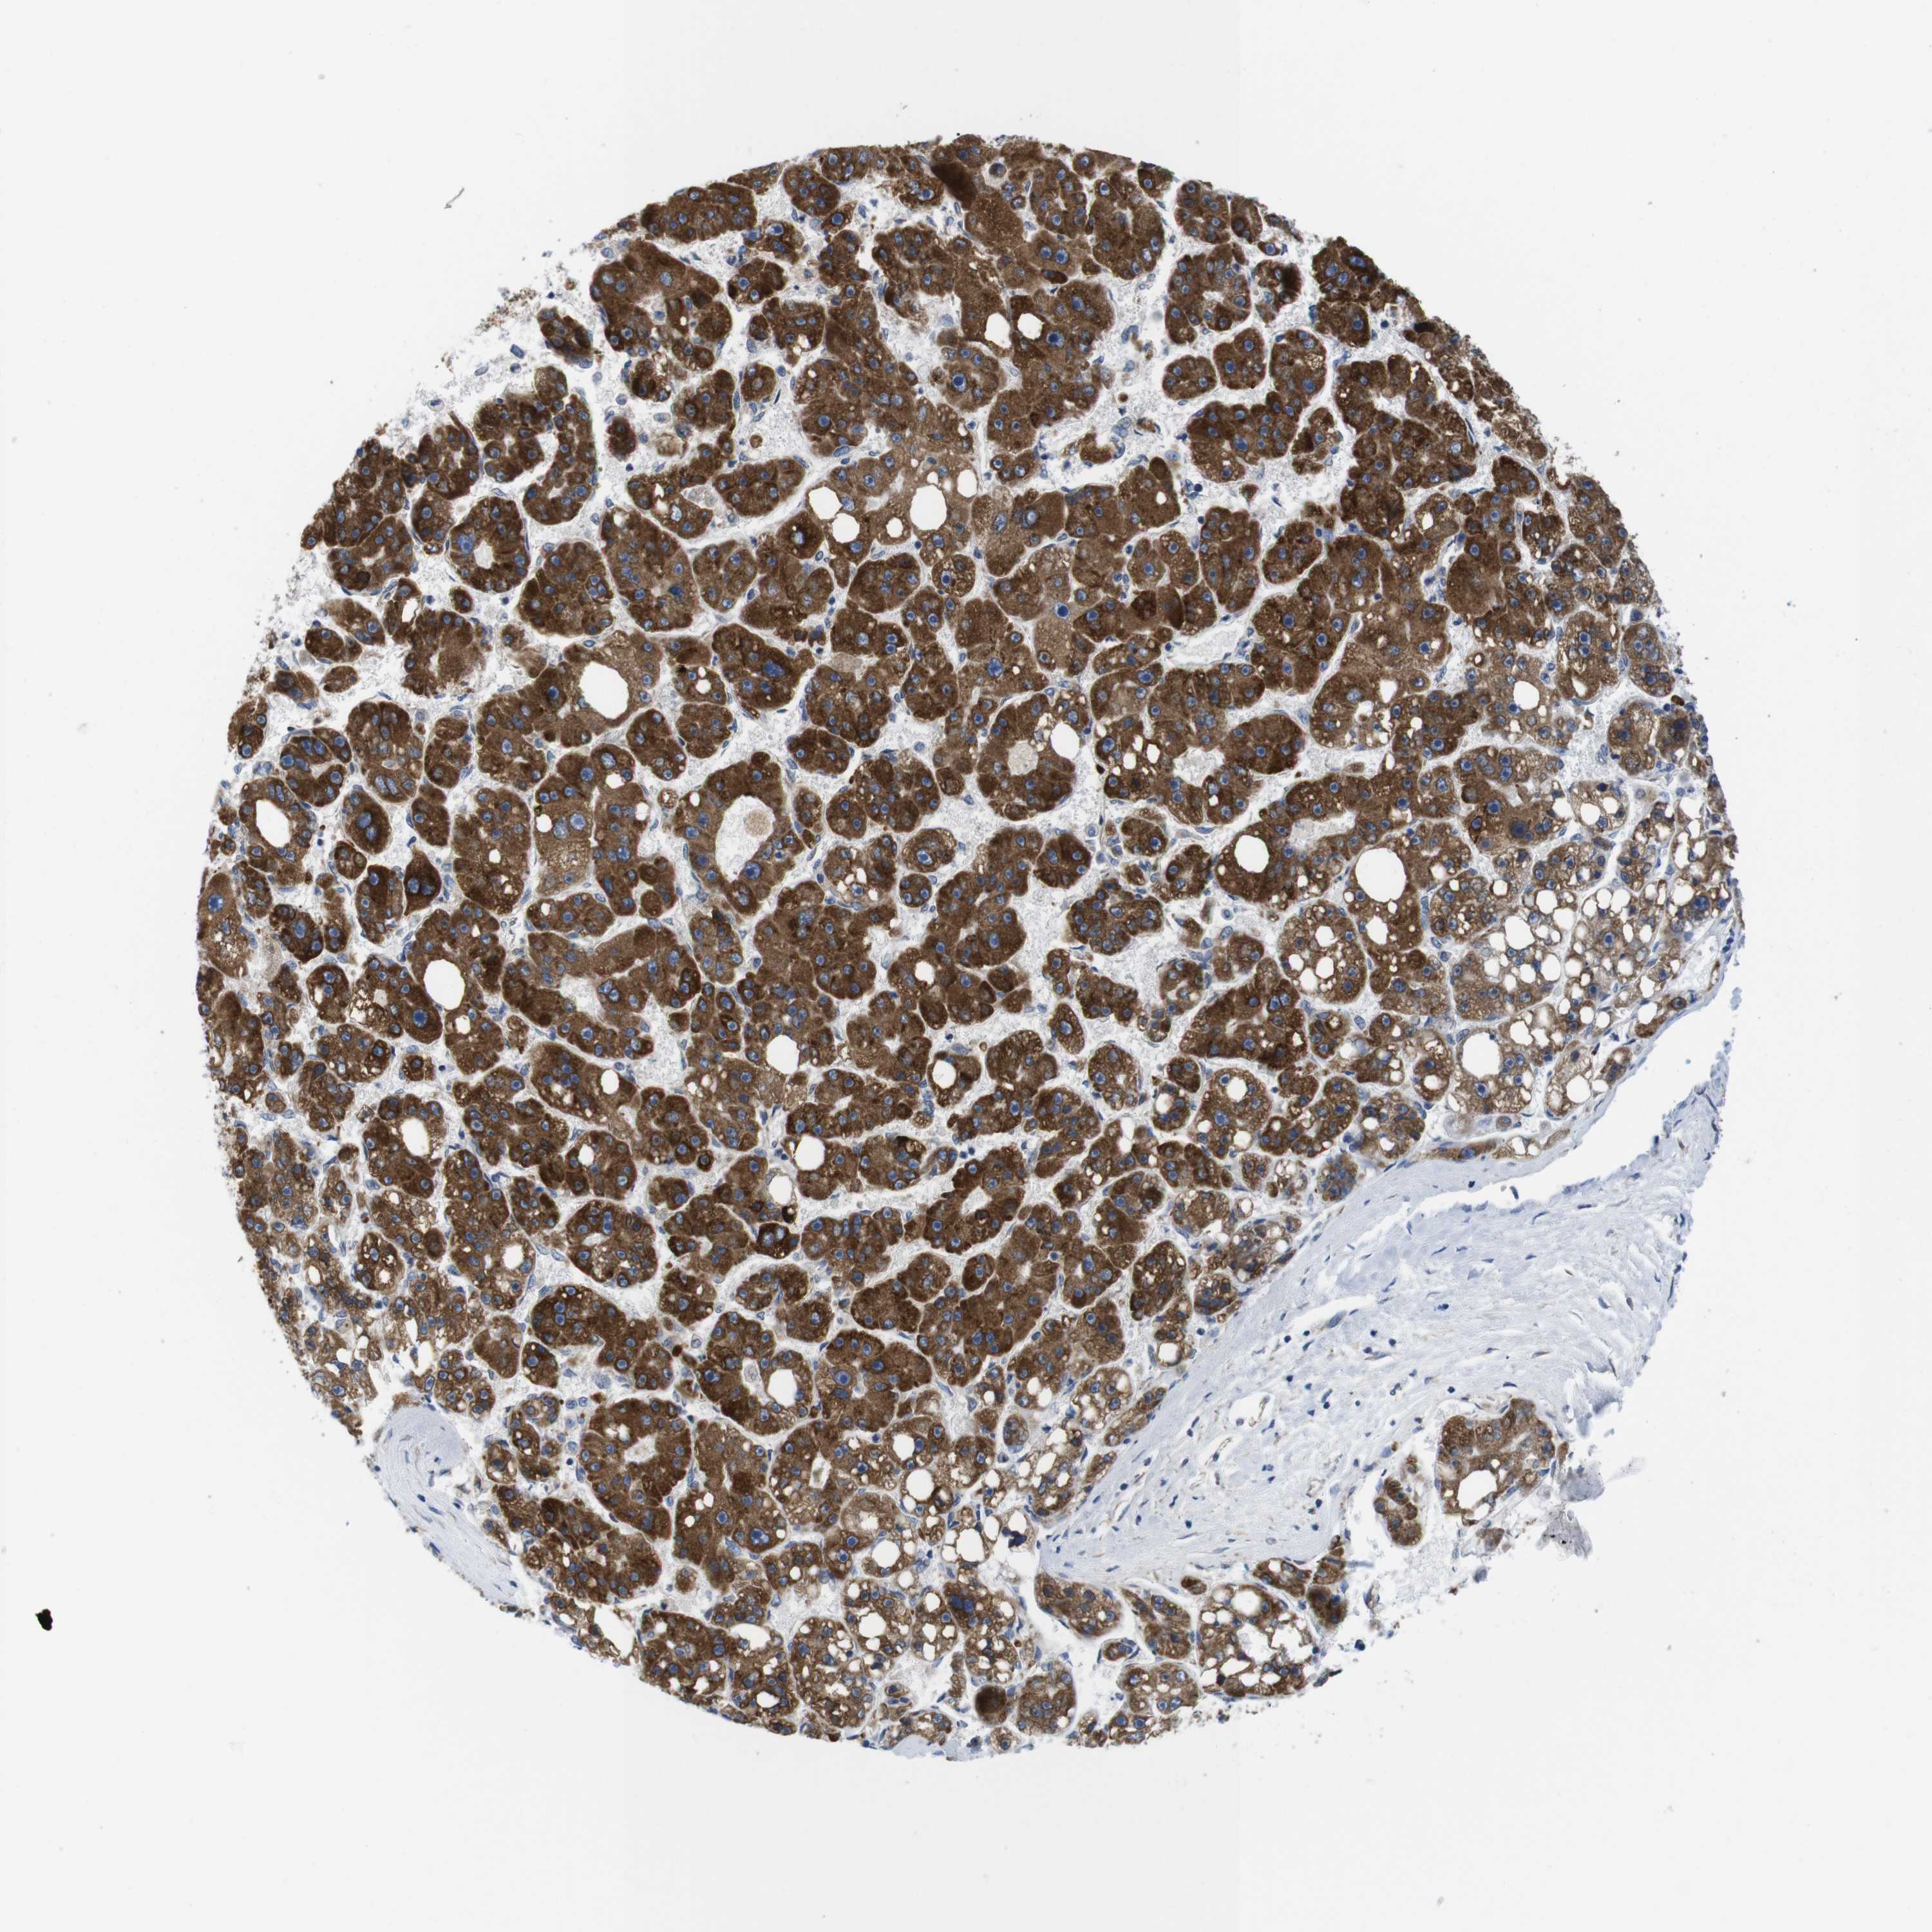

LIVER CANCER - Protein expressioni

A mouse-over function shows sample information and annotation data. Click on an image to view it in a full screen mode. Samples can be filtered based on level of antibody staining by selecting one or several of the following categories: high, medium, low and not detected. The assay and annotation is described here.

Note that samples used for immunohistochemistry by the Human Protein Atlas do not correspond to samples in the TCGA dataset.

Antibody stainingi

Antibody staining in the annotated cell types in the current human tissue is reported as not detected, low, medium, or high, based on conventional immunohistochemistry profiling in selected tissues. This score is based on the combination of the staining intensity and fraction of stained cells.

Each image is clickable and will lead to virtual microscopy that enables deeper exploration of all samples and also displays staining intensity scores, fraction scores and subcellular localization as well as patient and tissue information for each sample.

Antibody HPA014837

Staining

High

Medium

Low

Not detected

Intensity

Strong

Moderate

Weak

Negative

Quantity

>75%

75%-25%

<25%

None

Location

Nuclear

Cytoplasmic/membranous

Cytoplasmic/membranous,nuclear

Cholangiocarcinoma

Carcinoma, Hepatocellular, NOS